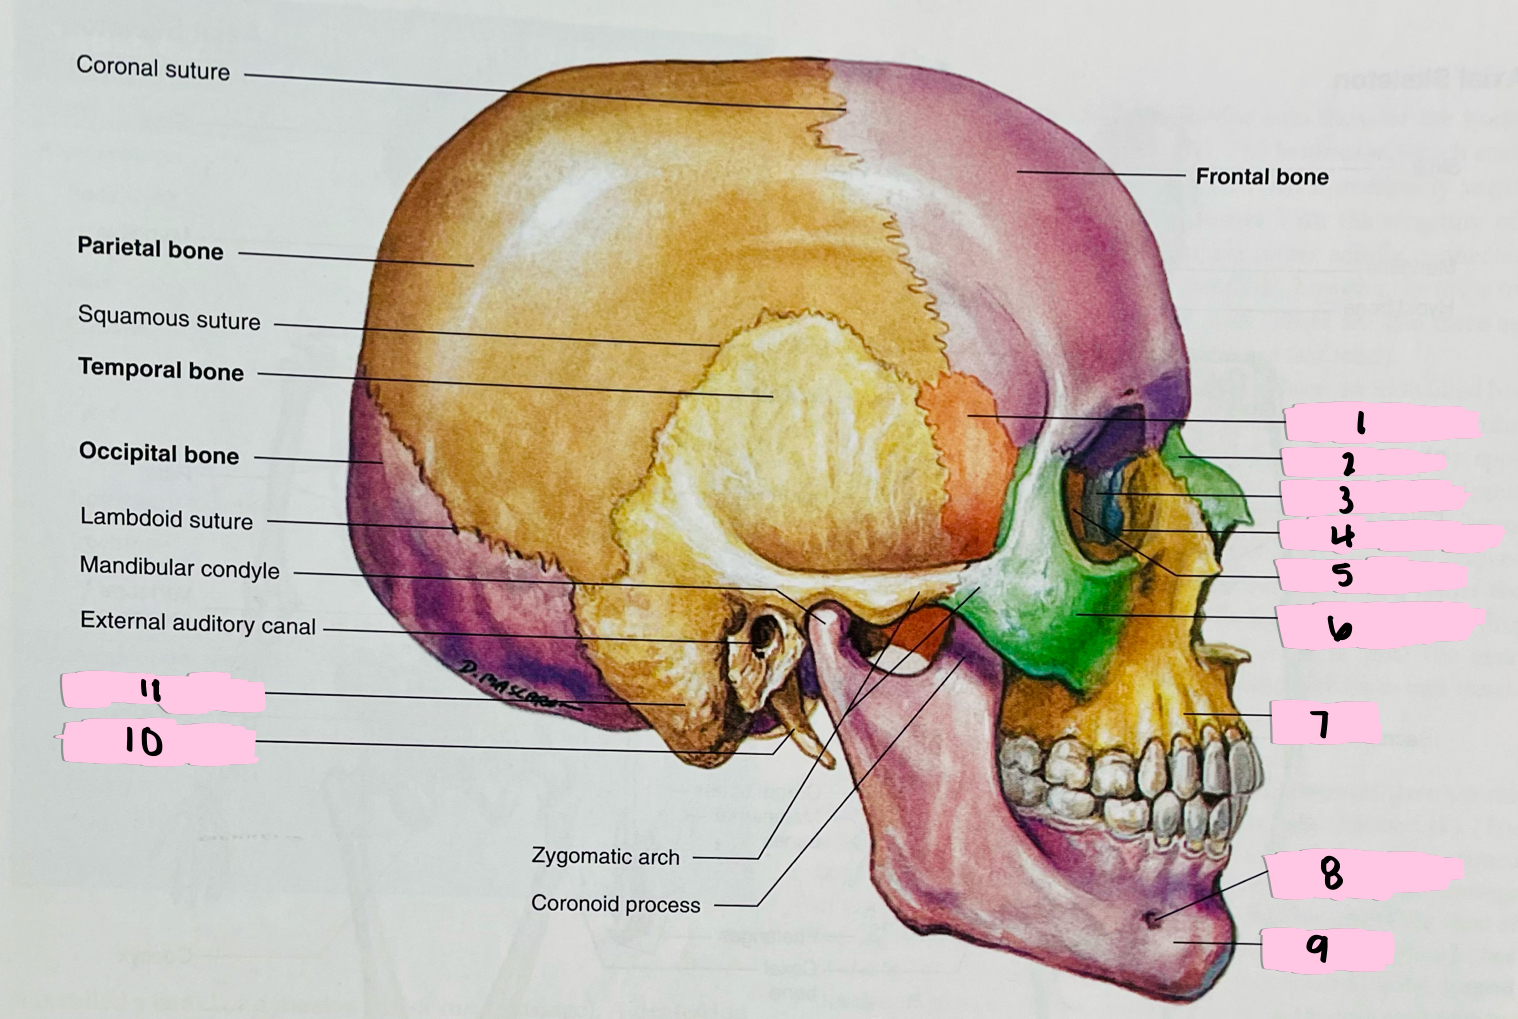

What is 1 pointing to?

Sphenoid bone

What is 2 pointing to?

Nasal bone

What is 3 pointing to?

Lacrimal bone

What is 4 pointing to?

Nasolacrimal canal

What is 5 pointing to?

Ethmoid bone

What is 6 pointing to?

Zygomatic bone

What is 7 pointing to?

Maxilla

What is 8 pointing to?

Mental foramen

What is 9 pointing to?

Mandible

What is 10 pointing to?

Styloid process

What is 11 pointing to?

Mastoid process